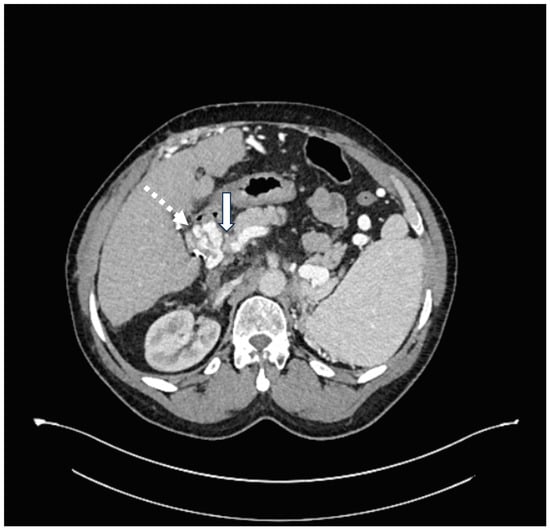

Given the extensive nature of the HAPVF and his hepatic decompensation, the decision was made to treat the fistula with transcatheter embolization. His pre-operative lab work included a creatinine of 1.6 mg/dL, total bilirubin 1.48 mg/dL, platelets 51,000, and INR 1.35. Celiac arteriography revealed a dilated and extremely long and tortuous common and proper hepatic artery (Figure 2A). Hepatic arteriograms demonstrated a short-segment fistula between the right hepatic artery and the portal vein (Figure 2B,C). Close and central to the fistula were two significant branches of the right hepatic artery. Attempts were made to deploy a vascular plug into the fistula without success because the delivery sheath could not track along the tortuous hepatic artery. The initial placement of detachable coils resulted in unconstrained extension into the main portal vein, requiring their removal before deployment. Finally, detachable coils were deployed into the short-segment fistula (one Concerto 2 mm and one Concerto 8 mm coil). A post-embolization arteriogram showed occlusion of the HAPVF without injury to the two adjacent normal right hepatic arteries (Figure 2D). His bilirubin decreased from 1.48 to 1.02 mg/dL. Post-procedure MRI found successful closure of the HAPVF with patent hepatic arteries and portal vein without early enhancement, but rather with occlusion of the main, left, and right portal veins. There were periportal collaterals suggesting cavernous transformation. We presume that the hepatic artery had been providing retrograde flow into the portal system, which subsequently thrombosed after fistula closure. The splenic vein and superior mesenteric vein remained patent. A CT scan with contrast performed 4 years after embolization shows persisting portal vein thrombosis and the collateralization of portal venous inflow (Figure 3).

Figure 3. Post-procedure CT scan of abdomen performed 4 years after HAPVF embolization. Solid arrow indicates portal vein thrombosis. Dashed arrow indicates collateral blood vessel at hepatic hilum.